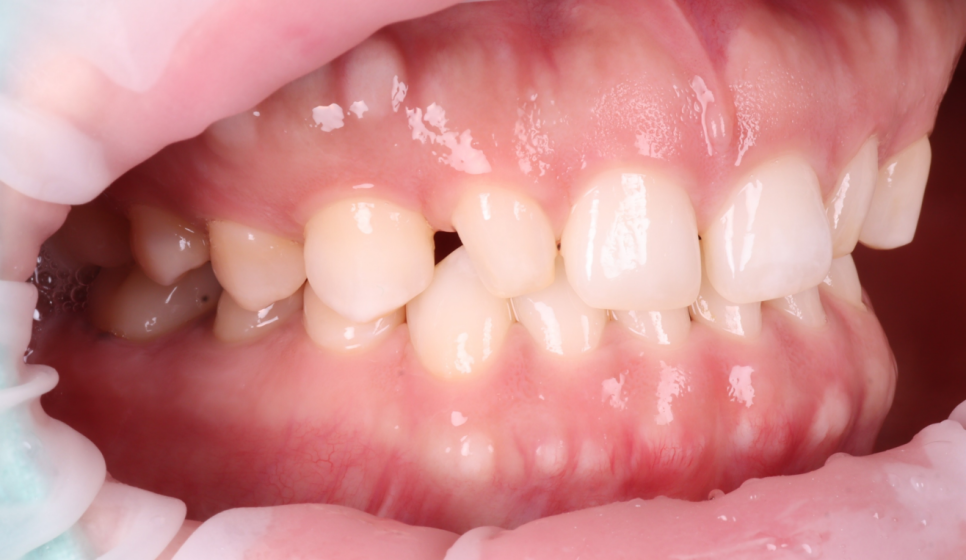

앞니 왜소치 레진 전, 후 / 촬영일 : 251203 / 251203

환자분이 거울을 보시고 “생각보다 티가 안 나네요?”라고 하셨을 때 이 방향이 맞다는 확신이 들었어요ㅎㅎ

2주 뒤 내원하셔서 환자분이 가운데 앞니 이야기를 꺼내셨어요.

“이 사이 벌어진 것도 치료하고 싶어요.”

사이에 벌어진 공간도 자연스럽게 메워드렸습니다.

촬영일 : 260103

미세한 부분까지 조정해 드렸어요.